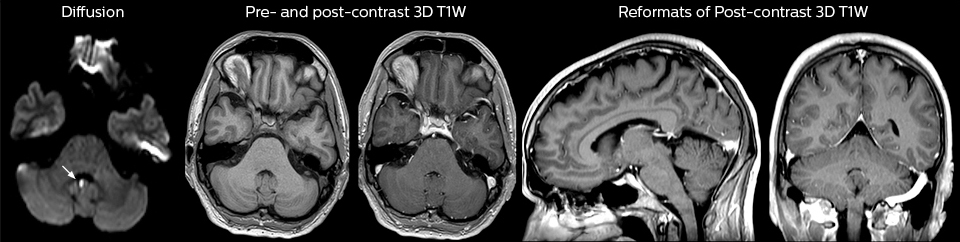

Guidance on appropriate use of MRI

A range of protocol sheets was developed to help ensure that referring physicians order the most appropriate MRI exam. The optimized MRI protocols also include 3D contrast-enhanced imaging, allowing neurosurgeons to comfortably use the isotropic data in the operating room while performing stereotaxic surgery.

After the MRI scanning, the preliminary reports are made available to referring physicians more quickly than before, because that is what physicians need to make their decision on what to do with patient. Using a redesigned reporting process results in total

turnaround times that are similar to those of CT. Another of the changes introduced is that MRI safety screening data are retrieved from the hospital information system, saving approximately 30 minutes.